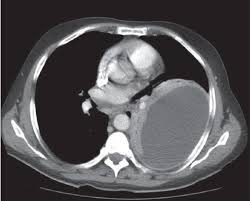

Ultrasound findings are relevant for pleural infection as in heavily septated or loculated effusions, the biochemical results can be different in the discrete areas, so can give falsely reassuring results. Malignant pleural effusion, lymphangitis carcinomatosa: In patients with symptomatic malignant pleural effusions with nonexpandable lung, failed pleurodesis, or loculated effusion, we suggest the use of ipcs over chemical pleurodesis. Rather than layering laterally and blunting of the costophrenic angle, the pleural fluid lies almost exclusively betw. Nov 28, 2018 · pericardial fluid drainage can be performed by percutaneous catheter drainage or open surgical approach. The parietal pericardium (arrow) clearly separates the loculated pericardial effusion (∗) from the pleural effusion (p). 34 the fluid may accumulate due to overproduction from diseased pleura, obstruction of lymphatic channels, or atelectasis of adjacent lung. 30 effusions are also sometimes referred to as sonographically complex, which is an echogenic effusion with or without septations. The precise pathophysiology of fluid accumulation varies according to underlying aetiologies. R hydropneumothorax, r pleura mass (mpm), mesotheliomaasbestos: Individual patient characteristics (eg, loculated vs circumferential, recurrent pericardial effusion, need for pericardial biopsy and location of pericardial effusion) and local practice patterns aid in deciding the optimal method of drainage. Help for veterans · speak to a doctor · free book on mesothelioma Pleural effusions are a common medical problem with more than 50 recognised causes including disease local to the pleura or underlying lung, systemic conditions, organ dysfunction and drugs.1 pleural effusions occur as a result of increased fluid formation and/or reduced fluid resorption.

Help for veterans · speak to a doctor · free book on mesothelioma Posterior effusion, loculated, empyema, ultrasound, parapneumonic effusion, streptococcus milleri: R hydropneumothorax, r pleura mass (mpm), mesotheliomaasbestos: Ultrasound findings are relevant for pleural infection as in heavily septated or loculated effusions, the biochemical results can be different in the discrete areas, so can give falsely reassuring results. Help for veterans · speak to a doctor · free book on mesothelioma Nov 28, 2018 · pericardial fluid drainage can be performed by percutaneous catheter drainage or open surgical approach. Malignant pleural effusion, lymphangitis carcinomatosa: Learn about the symptoms & causes of pleural effusions and pleural mesothelioma. Pleural effusions are a common medical problem with more than 50 recognised causes including disease local to the pleura or underlying lung, systemic conditions, organ dysfunction and drugs.1 pleural effusions occur as a result of increased fluid formation and/or reduced fluid resorption. The precise pathophysiology of fluid accumulation varies according to underlying aetiologies. In patients with symptomatic malignant pleural effusions with nonexpandable lung, failed pleurodesis, or loculated effusion, we suggest the use of ipcs over chemical pleurodesis. The parietal pericardium (arrow) clearly separates the loculated pericardial effusion (∗) from the pleural effusion (p). Subpulmonic effusions (also known as subpulmonary effusions) are pleural effusions that can be seen only on an erect projection.